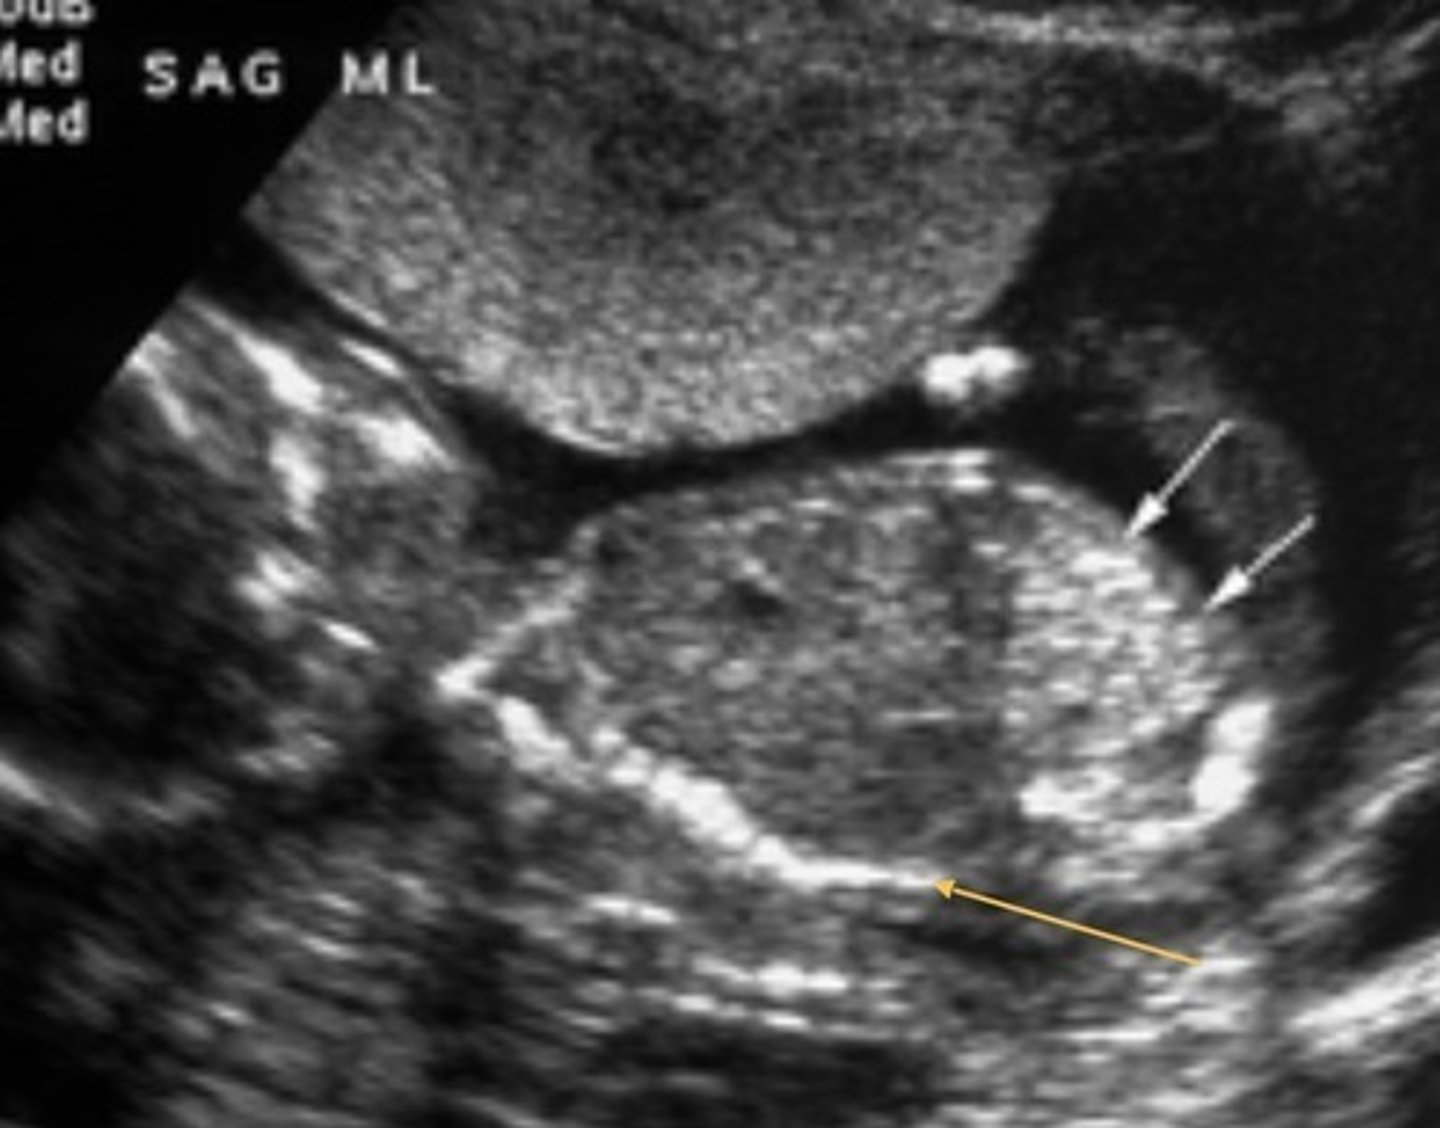

Potter's Syndrome Type I - Polycystic Kidney Disease

Bilateral micro cysts

Bilateral enlarged, echogenic kidneys

Empty bladder